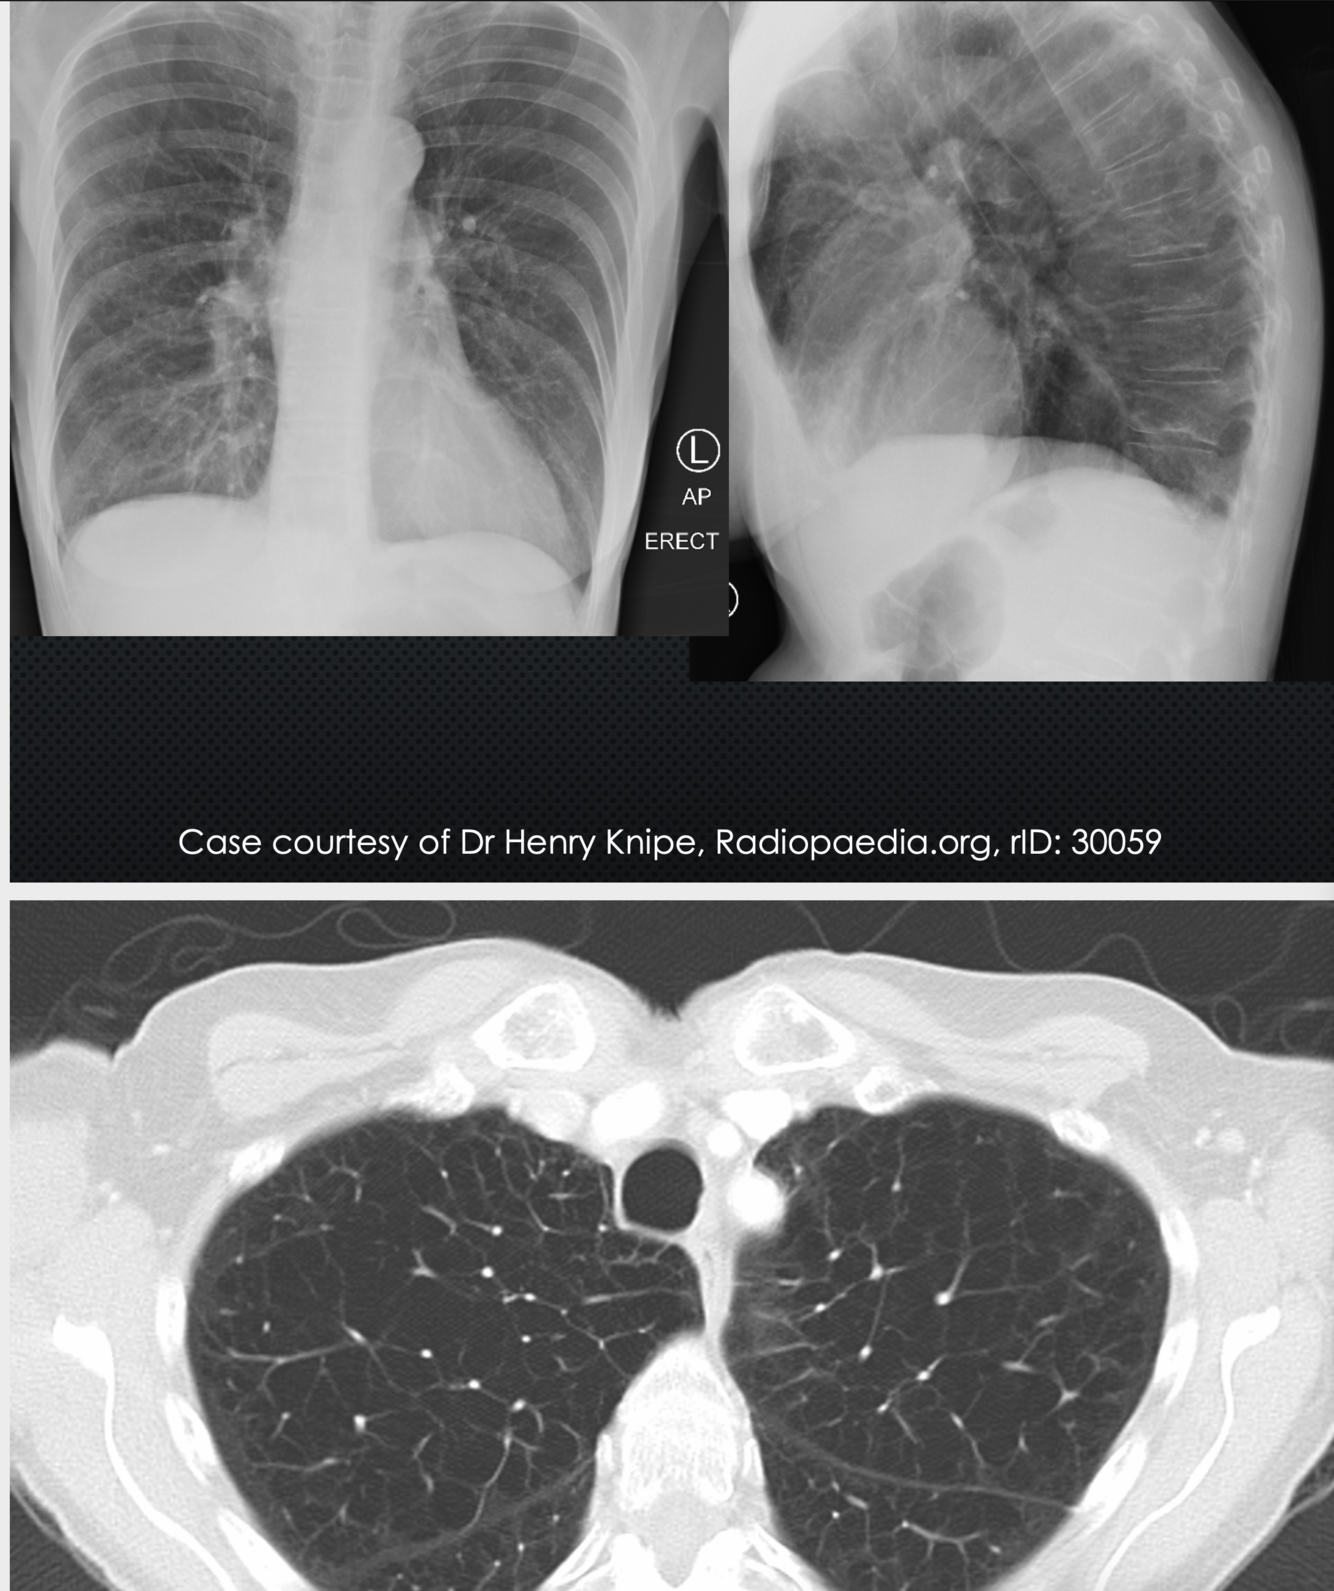

75M with progressive dyspnea/cough for 6 months

• Hypertension, 20pack-yr ex-smoker

• No history of CTD/malignancies/cardiac disease

• Retired librarian

• Meds: HCTZ. No allergies

Vitals normal • No H&N adenopathy • Resp exam: bibasilar crackles • Normal CV exam, clubbing on fingers.

thick fibrosis on the periphery of the lung.

• Most common ILD • Characteristic pathology can confirm the diagnosis

• Some cases can be diagnosed with a very

distribution of honeycomb lung for UIP